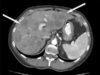

**emagrecimento + ictericiai obstrutiva + vesicula palpável = neoplassia periampolar** **neoplasia de cabeça pancreática ( imagem d )** **lembrar que antes da cirurgia devemos fazer alivio da ictericia e suporte nutricional.**